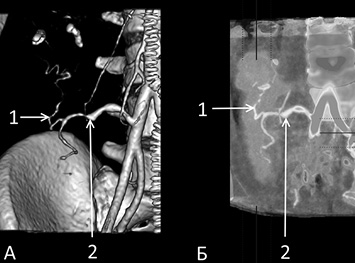

Трёхмерная реконструкция при компьютерной томографии (КТ) с контрастным усилением и КТ-перфузия позволили нам объективно доказать достаточную васкуляризацию паренхимы ТПЖ и равномерное кровоснабжение трансплантата по системе коллатералей между селезёночной и верхней брыжеечной артериями (рис. 3).

Рис. 3. (А) Трёхмерная реконструкция при компьютерной томографии (КТ) и (Б) КТ-перфузия трансплантата поджелудочной железы с изолированным кровоснабжением по селезёночной артерии: 1 — внутриорганные артериальные коллатерали; 2 — a. lienalis

Количественная оценка внутриорганного кровотока в исследованных ТПЖ также продемонстрировала достаточный уровень кровоснабжения органа изолированно по системе селезёночной артерии. Так, медианы объёмной скорости кровотока в ТПЖ составили: в головке — 124 [110; 160], в теле — 124 [113; 134], в хвосте — 118 [106; 132] мл/мин/100 г; медианы объёмного кровотока: в головке — 38 [32; 46], в теле — 36 [30; 51], в хвосте — 43 [37; 49] мл/мин. Медиана времени пиковой концентрации контраста в трансплантатах составила 21 [15; 26] с.